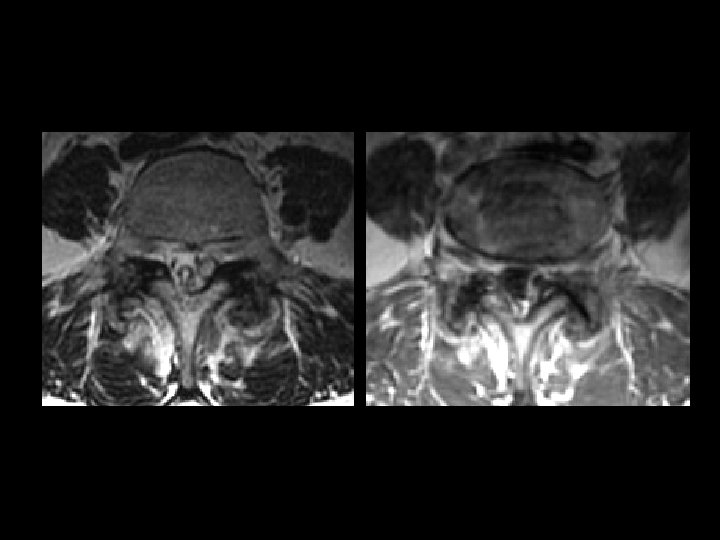

Synovial Cyst of the Lumbar Spine • • • Findings: – Low T 1, high T 2 extradural lesion contiguous with the facet joint – Surrounding enhancement – Mass effect Associated with degenerated joints – 75% at L 4 -5 Typically posterolateral Contents variable – clear fluid, calcium, hemorrhage ddx: – Migrated herniated disc – Perineural cyst (close to nerve root) – Schwannoma (low sig capsule) – Hematoma